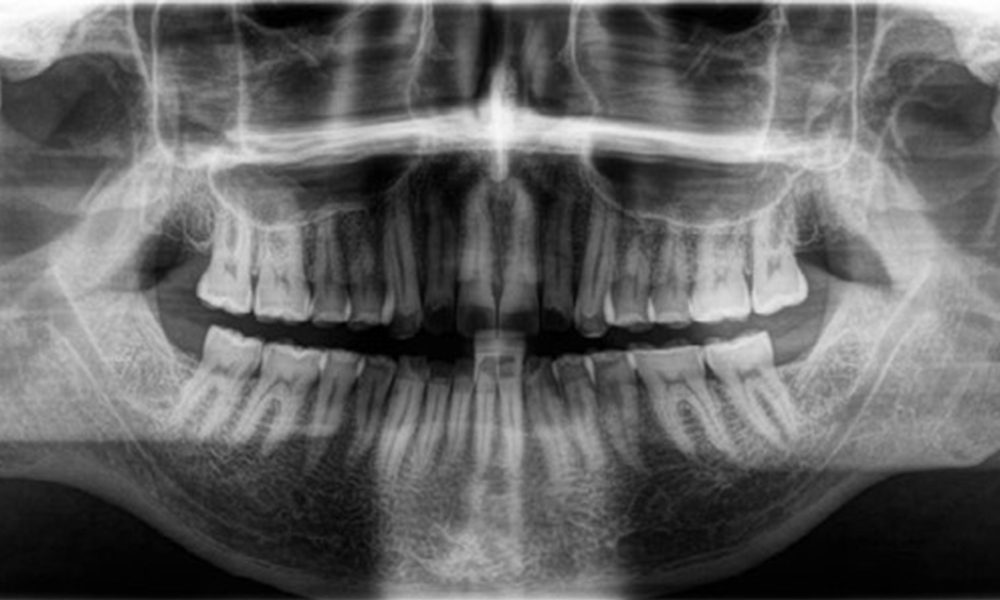

Résultats radiologiques

Une denture adulte complète, sans carie ni perte osseuse radiologiquement reconnaissable, a été observée (Fig. 6). La perte radiologique d'émail et de cuspides était particulièrement évidente sur les 36 et 37.

Radiographie panoramique

Fig. 6: Radiographie panoramique, © Dr R. Krapf